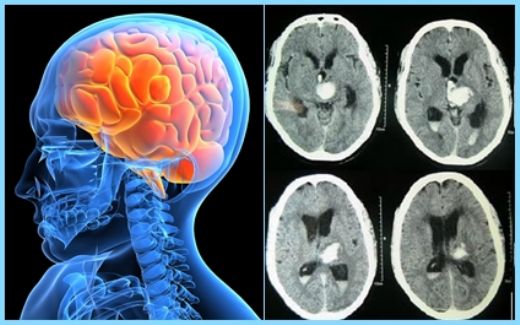

Beyin Kanaması Sonrası Ödem Belirtileri Ve TedavisiBeyin kanaması, beyin dokusunda kanamalara neden olan bir durumdur ve genellikle travma, hipertansiyon veya damar anormallikleri gibi çeşitli sebeplerle meydana gelir. Beyin kanaması sonrasında, hasar gören bölgedeki doku şişebilir; bu duruma "ödem" denir. Ödem, beyin kanaması sonrası ortaya çıkan önemli bir komplikasyondur ve hastanın genel durumunu ciddi şekilde etkileyebilir. Bu makalede, beyin kanaması sonrası ödem belirtileri, nedenleri ve tedavi yöntemleri ele alınacaktır. 1. Beyin Kanaması ve Ödemin TanımıBeyin kanaması, beyin dokusu içinde veya çevresinde kan birikmesine neden olan bir durumdur. Bu kanama, çeşitli nedenlerle ortaya çıkabilir ve beyin hücrelerinin hasar görmesine yol açabilir. Ödem ise, kanama sonrası beyin dokusunda sıvı birikmesi ile karakterize edilir. Beyin ödemi, beyin basıncını artırabilir ve bu durum, hayati tehlike oluşturabilir. 2. Ödem BelirtileriBeyin kanaması sonrası ödem belirtileri hastadan hastaya değişiklik gösterebilir; ancak genel olarak aşağıdaki semptomlar gözlemlenebilir:

Bu belirtiler, beynin farklı bölgelerinin etkilenmesine bağlı olarak değişebilir ve acil tıbbi müdahale gerektirebilir. 3. Ödemin NedenleriBeyin kanaması sonrası ödemin oluşmasının birkaç temel nedeni vardır:

4. Tedavi YöntemleriBeyin kanaması sonrası ödemin tedavisi, durumun ciddiyetine ve hastanın genel sağlık durumuna bağlı olarak değişiklik gösterebilir. Tedavi yöntemleri şunları içerebilir:

5. SonuçBeyin kanaması sonrası ödem, ciddi bir komplikasyon olup, erken teşhis ve tedavi hayati önem taşımaktadır. Hastaların belirtileri dikkate alarak zamanında tıbbi yardım almaları, iyileşme sürecini olumlu yönde etkileyebilir. Beyin sağlığı, genel sağlık açısından kritik bir öneme sahip olduğundan, önleyici tedbirler almak ve risk faktörlerini yönetmek de oldukça önemlidir. Ekstra BilgilerBeyin kanaması sonrası ödem ile ilgili yapılacak daha fazla araştırma, bu durumu daha iyi anlamamıza ve tedavi yöntemlerini geliştirmemize yardımcı olacaktır. Ayrıca, rehabilitasyon süreci, hastaların günlük yaşamlarına dönmelerine yardımcı olmak için önemlidir. Bu nedenle, multidisipliner bir yaklaşım benimsemek ve nöroloji, beyin cerrahisi, fizyoterapi gibi alanların iş birliği içinde çalışması gerekmektedir. |